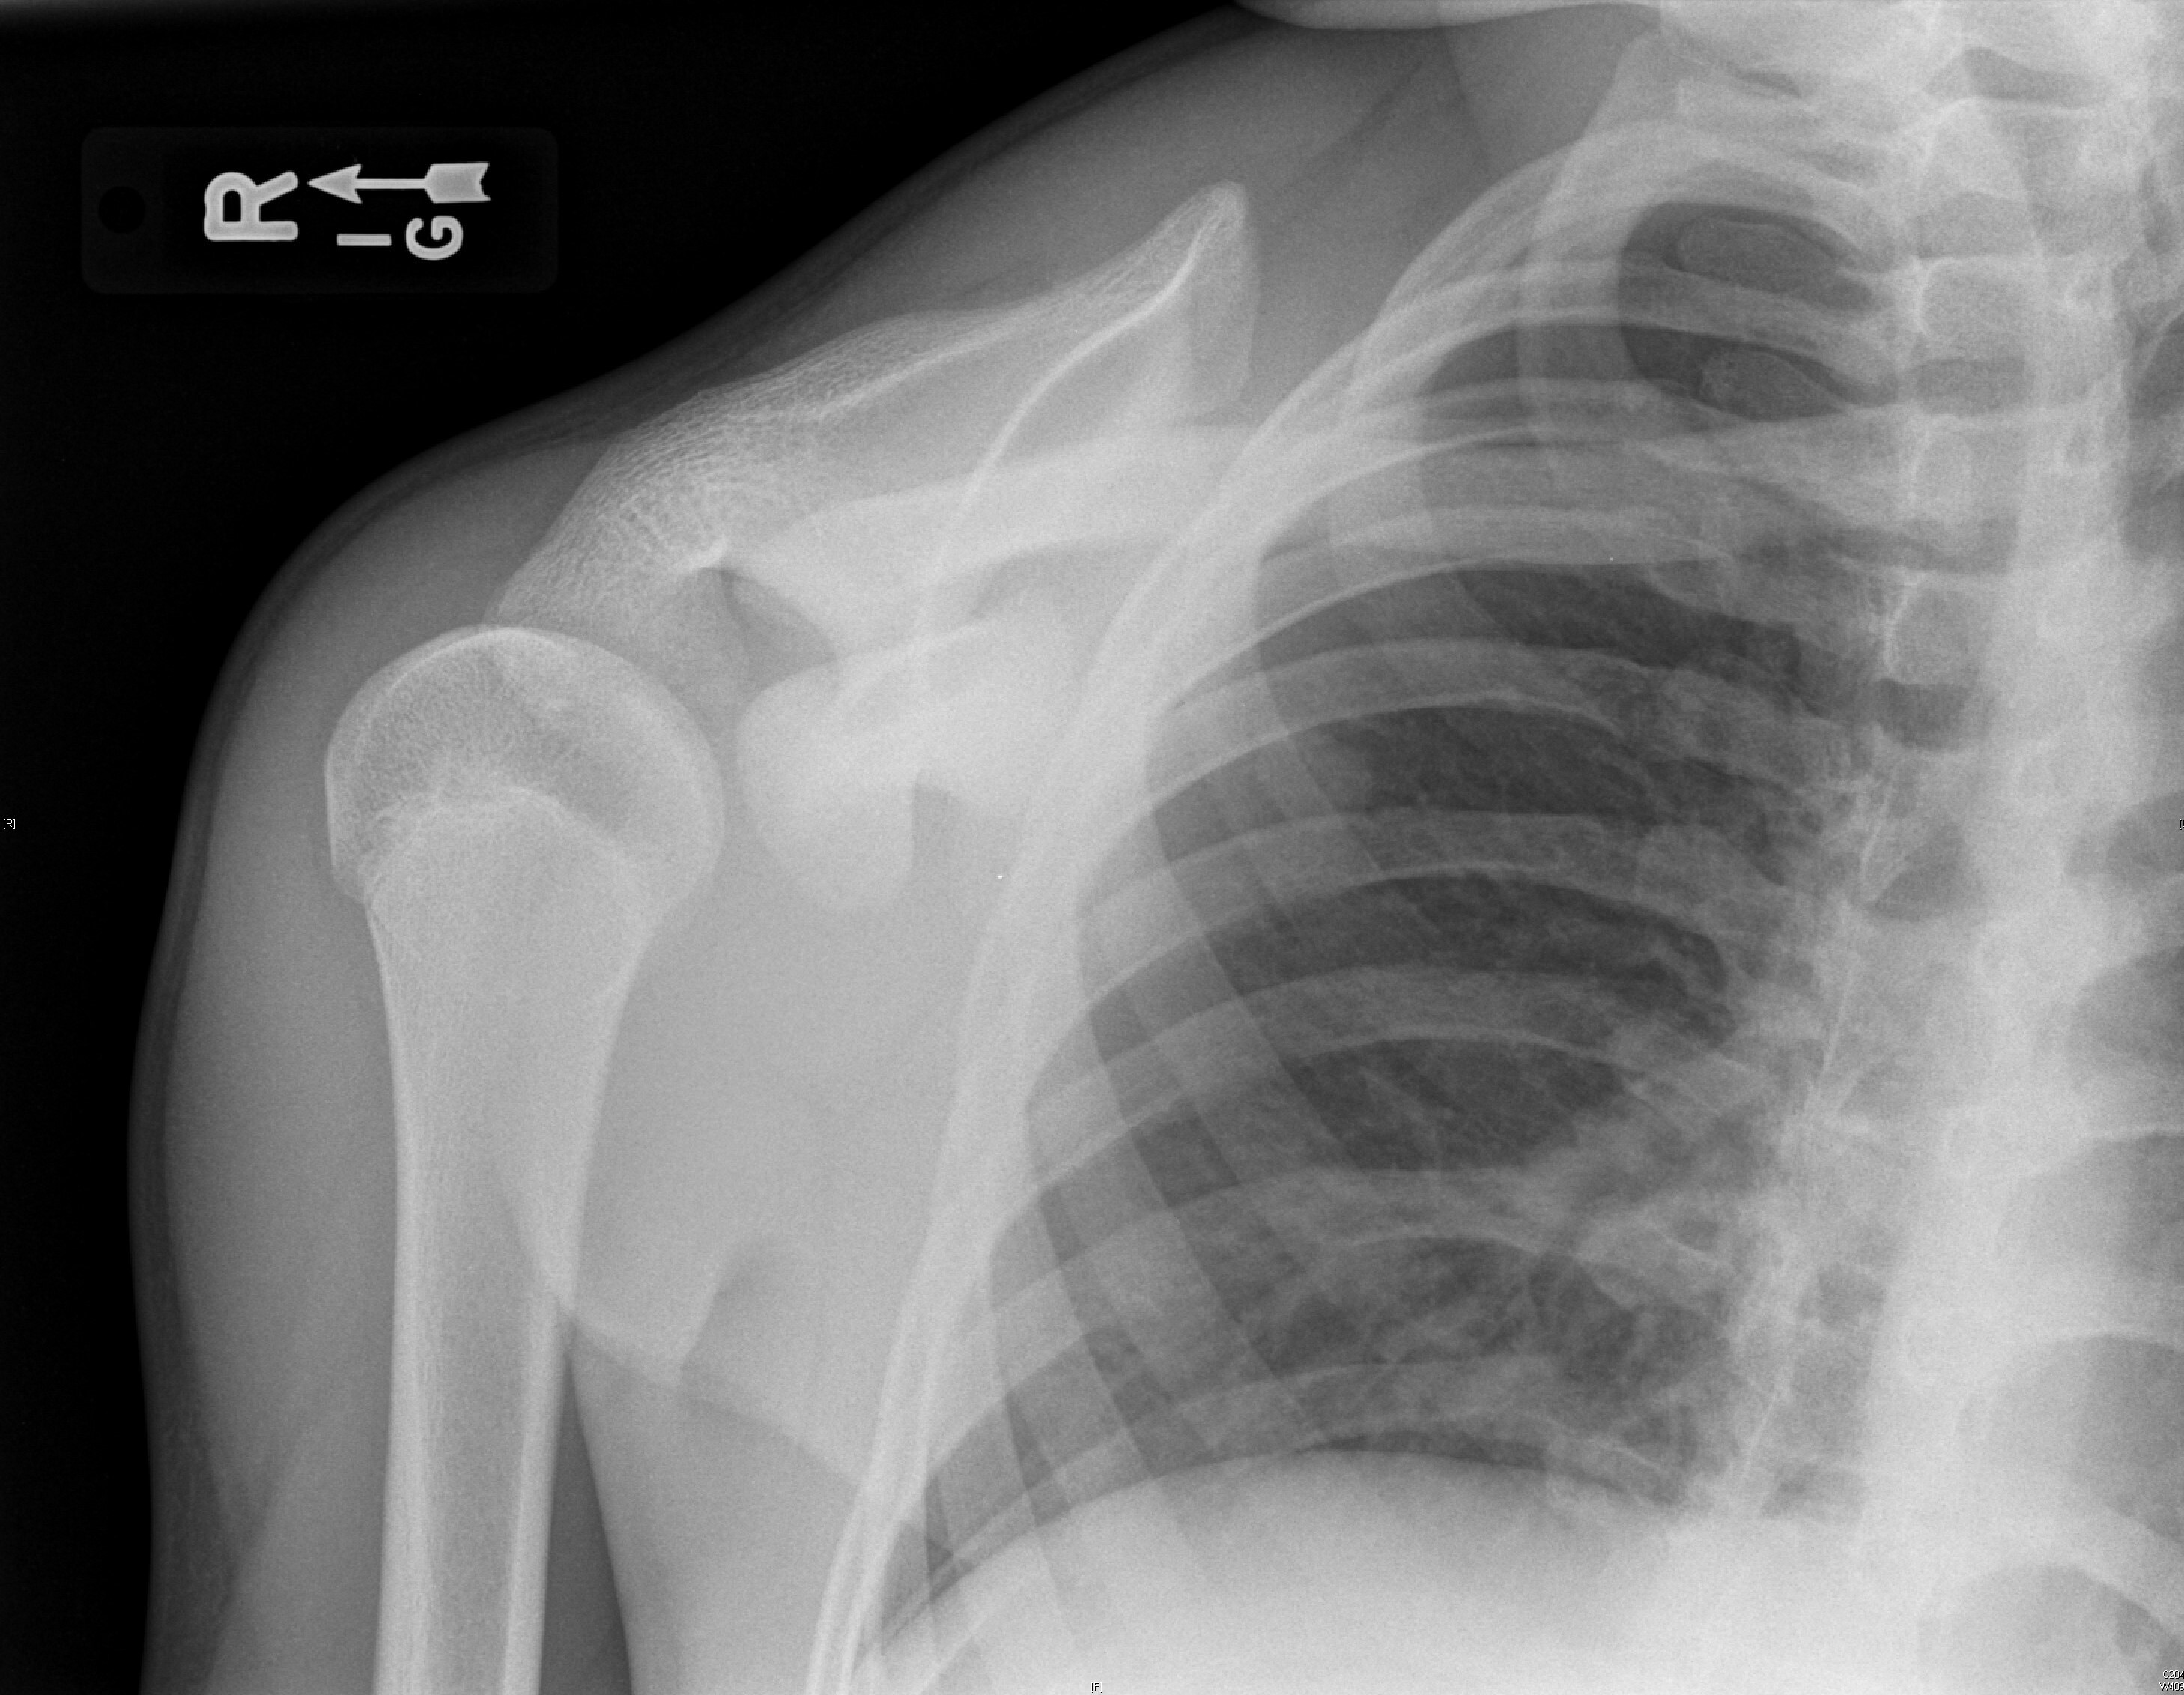

Posterior dislocations are easy to miss because the arm is in internal rotation and adduction. On AP radiograph, the posteriorly dislocated and internally rotated humeral head creates a “light bulb” sign, which may be noted. Nonetheless, posterior dislocation will be viewed best on the axillary view. (See Figures 3 and 4.) Posterior dislocations are at higher risk of surgical neck fracture, reverse Hill-Sachs lesions, and rotator cuff injuries.47,48

Figure 3. Posterior Dislocation Anteroposterior View |

![]() |

Source: Used with permission from J. Stephan Stapczynski, MD. |